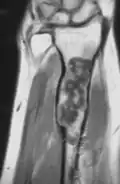

Magnetic resonance imaging (MRI), ultrasound, and scintigraphy are generally not practical for diagnostic purposes. X-rays are not as effective in the monitoring or evaluation of enchondromas due to frequent localized changes also sometimes due to the large number of enchondromas. MRI can sometimes however be used to monitor and evaluate symptomatic lesions in the case of potential malignant transformations.

Corticoplasty has been shown to have success in treating hand lesions and deformities while retaining normal function.[23][24] The surgery utilizes the removal of tissue (curettage) and bone reconstruction in order to remove enchondromas and improve cosmetic appearance. Many cases of corticoplasty have been shown improvement in appearances while maintaining function. Recurrence of enchondromas was observed in some cases. In cases of Ollier disease, early surgical treatment of enchondromas in the hand is recommended.